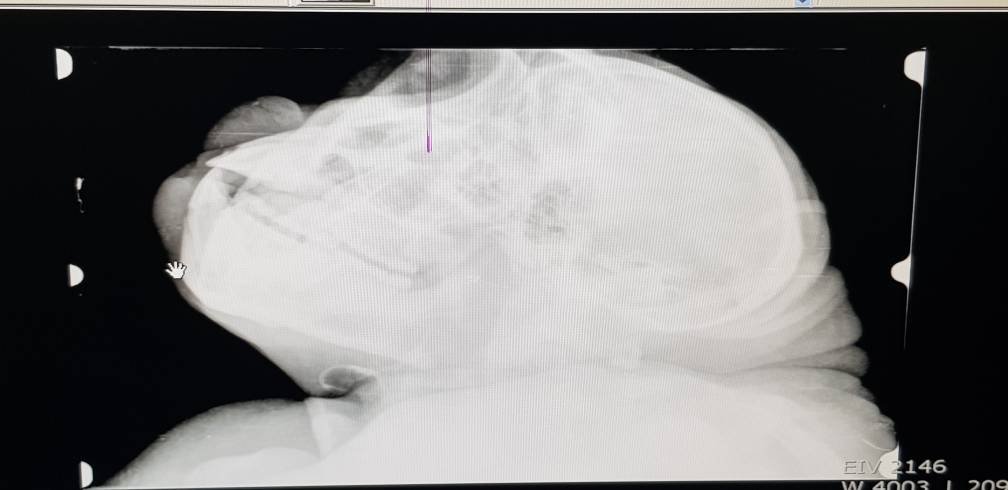

Tongo à nouveau anesthésié

TONGO est le jeune mâle qui nous faisait des abcès à répétition au niveau du cou en 2017. grâce à l’intervention du Dr Ainare en septembre dernier, nous pensions avoir trouvé la source de ce mal: les deux incisives centrales supérieures étaient cariées et l’infection s’était propagée dans toute la zone ORL – d’où lesLireLire la suite « Tongo à nouveau anesthésié »